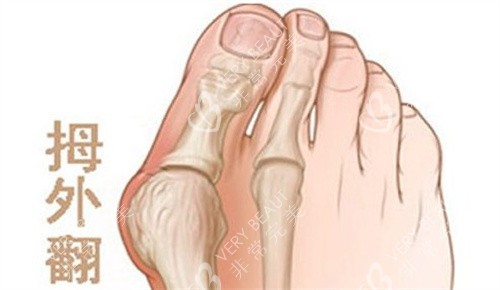

拇外翻,也就是我们常说的“大脚骨”,不仅影响脚部美观,还可能引发疼痛,影响日常行走。很多饱受拇外翻困扰的人会选择通过手术来矫正,然而,令人头疼的是,部分人在矫正后却出现了复发的情况。今天,就带大家揭秘拇外翻矫正后可能复发的3大原因。

比如,对于轻度拇外翻患者,如果采用了过于激进的手术方式,可能会破坏足部的正常结构和稳定性;而对于重度拇外翻患者,如果选择的手术方式矫正力度不够,就无法有效纠正畸形,术后复发的概率自然会增加。所以,在选择手术时,一定要找可靠的足踝外科医生,进行详细的检查和评估,制定个性化的手术方案。

此外,一些不良的生活习惯,如长期穿高跟鞋、尖头鞋等,会对足部造成持续的挤压和摩擦,增加拇外翻复发的可能性。还有一些患有类风湿性关节炎、痛风等疾病的患者,由于关节受到炎症的影响,也容易导致拇外翻复发。